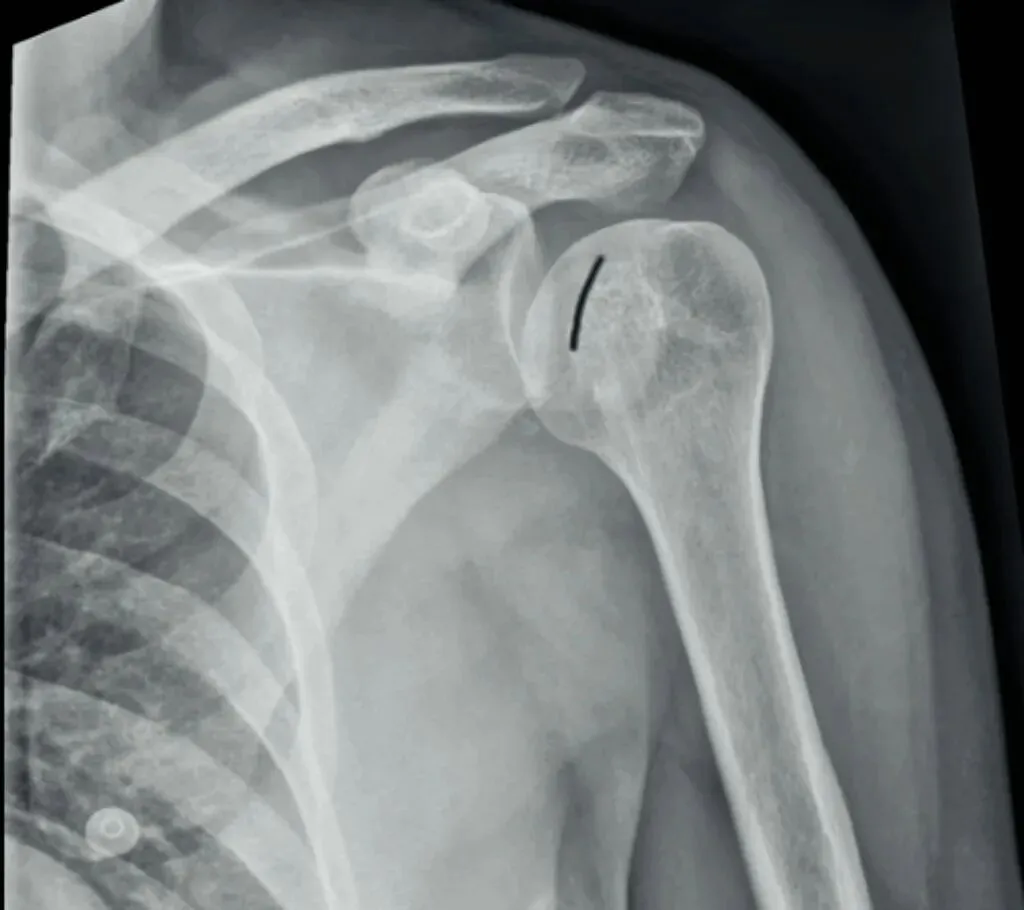

常可伴肱骨内旋,肱骨头投影变圆呈灯泡征。肱骨内旋后,大小结节投影有时候会形成一条折线,称M字征。

其次,我们要注意外伤患者不仅有肩关节脱位,有时还会伴随骨折出现。有一个很典型的影像学表现就是槽线征,当肱骨头撞击关节盂后缘,骨质形成压缩性骨折,表现为肱骨头内侧骨皮质与反Hill-Sachs骨折块形成的近乎平行线,称槽线征。

槽线征的识别对判断肱骨头内侧压缩性骨折至关重要。我们可以在肩关节的X线或者CT检查中清晰看到后脱位的肱骨头向关节窝的后方移位,同时也可显示肱骨头内侧受撞击形成的压缩性骨折(反Hill-Sachs骨折)。

需要注意出现槽线征时,盂肱关节间隙有时候狭窄,也有时候是增宽的,这也是在只有肩关节正位X线检查中比较容易出现漏诊的地方。